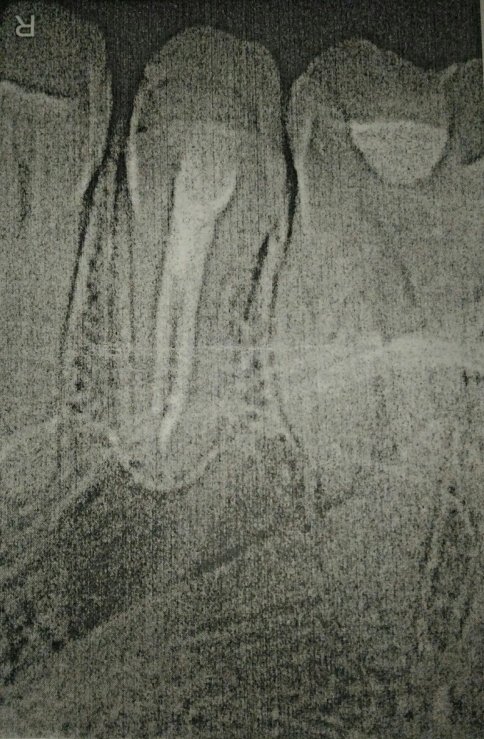

В подростковом возрасте мне сделали резекцию передних зубов из-за кисты. Но спустя примерно 15 лет над зубом образовался, на ощупь, шарик и очень неприятное напряжение под зубом. Я пошла к врачу, он отправил на снимок, но так и не смог мне помочь, и отправил к другому стоматологу, но попасть к нему я так и не смогла.

Вы не могли бы мне сказать, что это? И к кому мне нужно обратиться? У нас городок маленький и специалистов не так много.

У вас так называемый рецидив. Обратитесь к хирургу, думаю, данный зуб придется удалить.